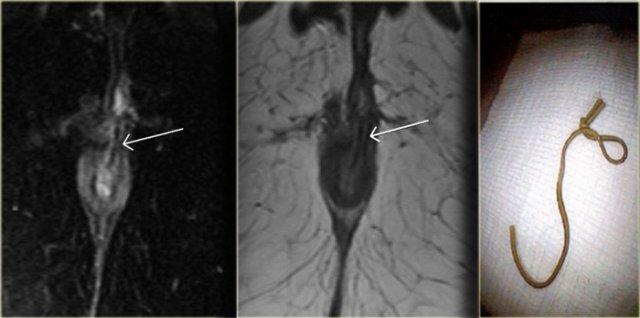

Bệnh nhân này đã được chẩn đoán trước đó là rò liên cơ thắt, với tổn thương niêm mạc ở vị trí 1 giờ.

Trong lòng đường rò có một cấu trúc dạng tuyến tính với tín hiệu thấp.

Đây là chỉ Seton đã được đặt vào để điều trị đường rò.